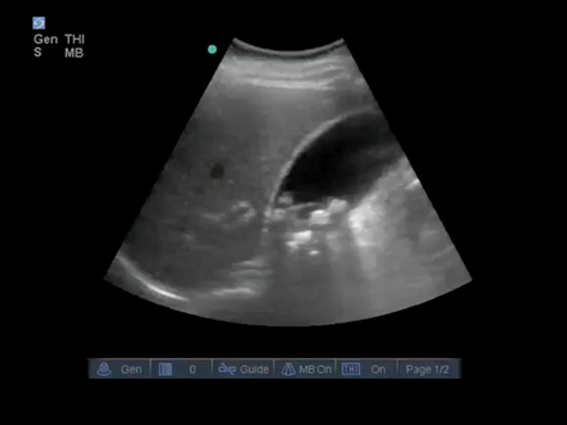

Gallbladder Clinical Indication Image